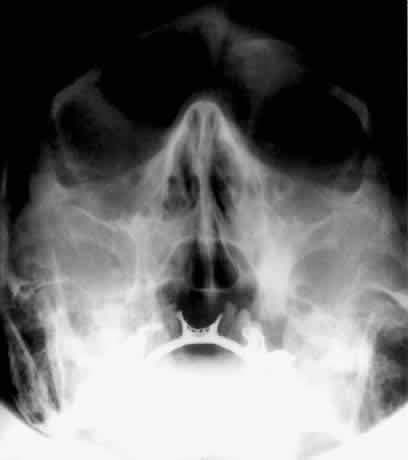

The posterior segment of the lateral wall courses posterior medially and can be seen in anterior projections such as the Caldwell view. This view allows direct visualization of the greater sphenoid wing contribution to the lateral wall. Bone density changes in the greater wing of the sphenoid, such as from a meningioma, can be detected. Fractures of the lateral orbital wall can occur from blunt trauma to the malar prominence. The zygomatic complex fracture (tripod) results from separation of the zygomatic-frontal, zygomatic-temporal, and the zygomatic-maxillary sutures. These fractures are associated with an inferior displacement of the malar prominence and a rounded lateral canthus (Figs. 8 and 9).

Fig. 8. A zygomatic complex fracture (tripod) after blunt trauma to the right cheek. Note the right zygoma is inferiorly displaced. (a, zygomatic-frontal suture separation; b, orbital rim disruption; c, opacification of maxillary sinus)

Fig. 9. Bilateral zygomatic complex and LeFort II fracture after reduction using fixation plates. Caldwell projection shows good alignment of orbital margin and zygomatic bones.